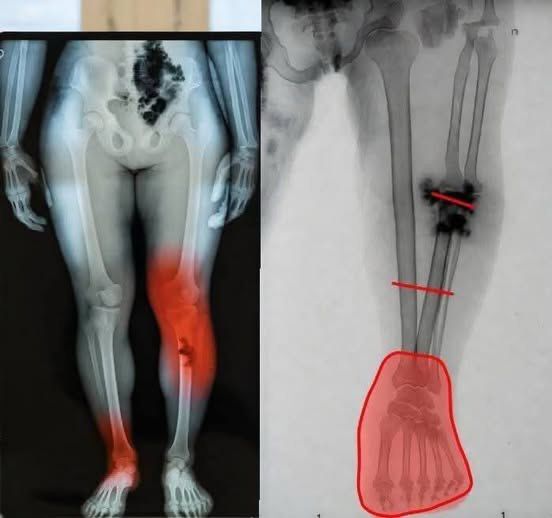

A recurring example involves dramatic posts claiming that people who received a COVID-19 vaccine may be at risk of severe illness. These posts often feature emotionally charged images, such as medical illustrations suggesting a syringe being injected directly into the heart. Accompanied by vague warnings like “If you got the COVID vaccine, you should know this,” such content spreads quickly and captures attention.

Fear-based health messaging is especially effective in this environment. Images that imply immediate danger—such as a syringe pointed at a heart—activate a natural instinct to protect oneself. Before viewers even read the accompanying text, the visual message has already created a sense of urgency.

For instance, some posts mention the condition known as myocarditis—a form of heart inflammation. When this medical term appears alongside dramatic images or warnings, it can give the impression of widespread risk. However, without details about frequency, severity, or comparison to other risks, the information becomes distorted.

One of the most discussed conditions is myocarditis. This involves inflammation of the heart muscle and was observed in a limited number of cases after certain mRNA vaccines, particularly among adolescent and young adult males.